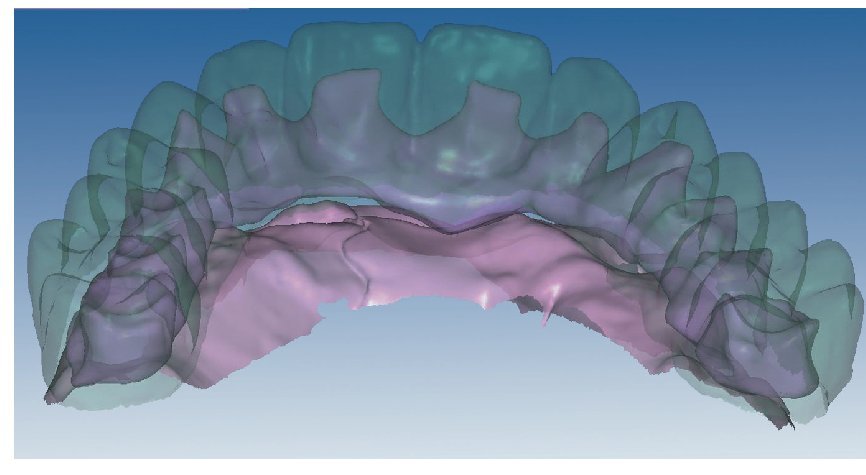

Mediante el uso de un escáner óptico de luz estructurada, los protocolos CAD registran los primeros datos relativos al modelo maestro con las correspondientes posiciones de implante (figs. 87 y 92). En el siguiente paso tiene lugar la digitalización de la planificación, previamente realizada en cera de escaneo matificada, de la restauración definitiva (figs. 88, 90 y 93). La subsiguiente conciliación de los datos mediante el uso del software de diseño dental permite al protésico planificar virtualmente el resto del procedimiento (figs. 89 y 91, 94 a 96) a partir del diseño de las estructuras (figs. 97 y 98).

Figs. 94 a 95. Planificación CAD de la estructura del maxilar inferior, en representación lingual y vestibular.

Figs. 96 a 98. El diseño definitivo de la estructura del maxilar inferior, desde distintas perspectivas.

Una vez aprobada la planificación, mediante el software CAD se transmiten los datos en formato STL (Standard Transformation Language o Stereolithography Language) a otro software CAM, el cual procesa nuevamente los datos suministrados para enviarlos en «idioma de máquina» a la fresadora (Zfx, ULTRASONIC 20, Denttec KG-SAS, Gargazon, Italia) encargada de confeccionar la estructura de titanio (figs. 98 y 99). La utilización de fresadoras industriales de cinco ejes para la confección de este tipo de prótesis garantiza un éxito seguro en cuanto a precisión de ajuste y pasivización, y evita casi todos los riesgos que pueden aparecer durante el colado protésico clásico.